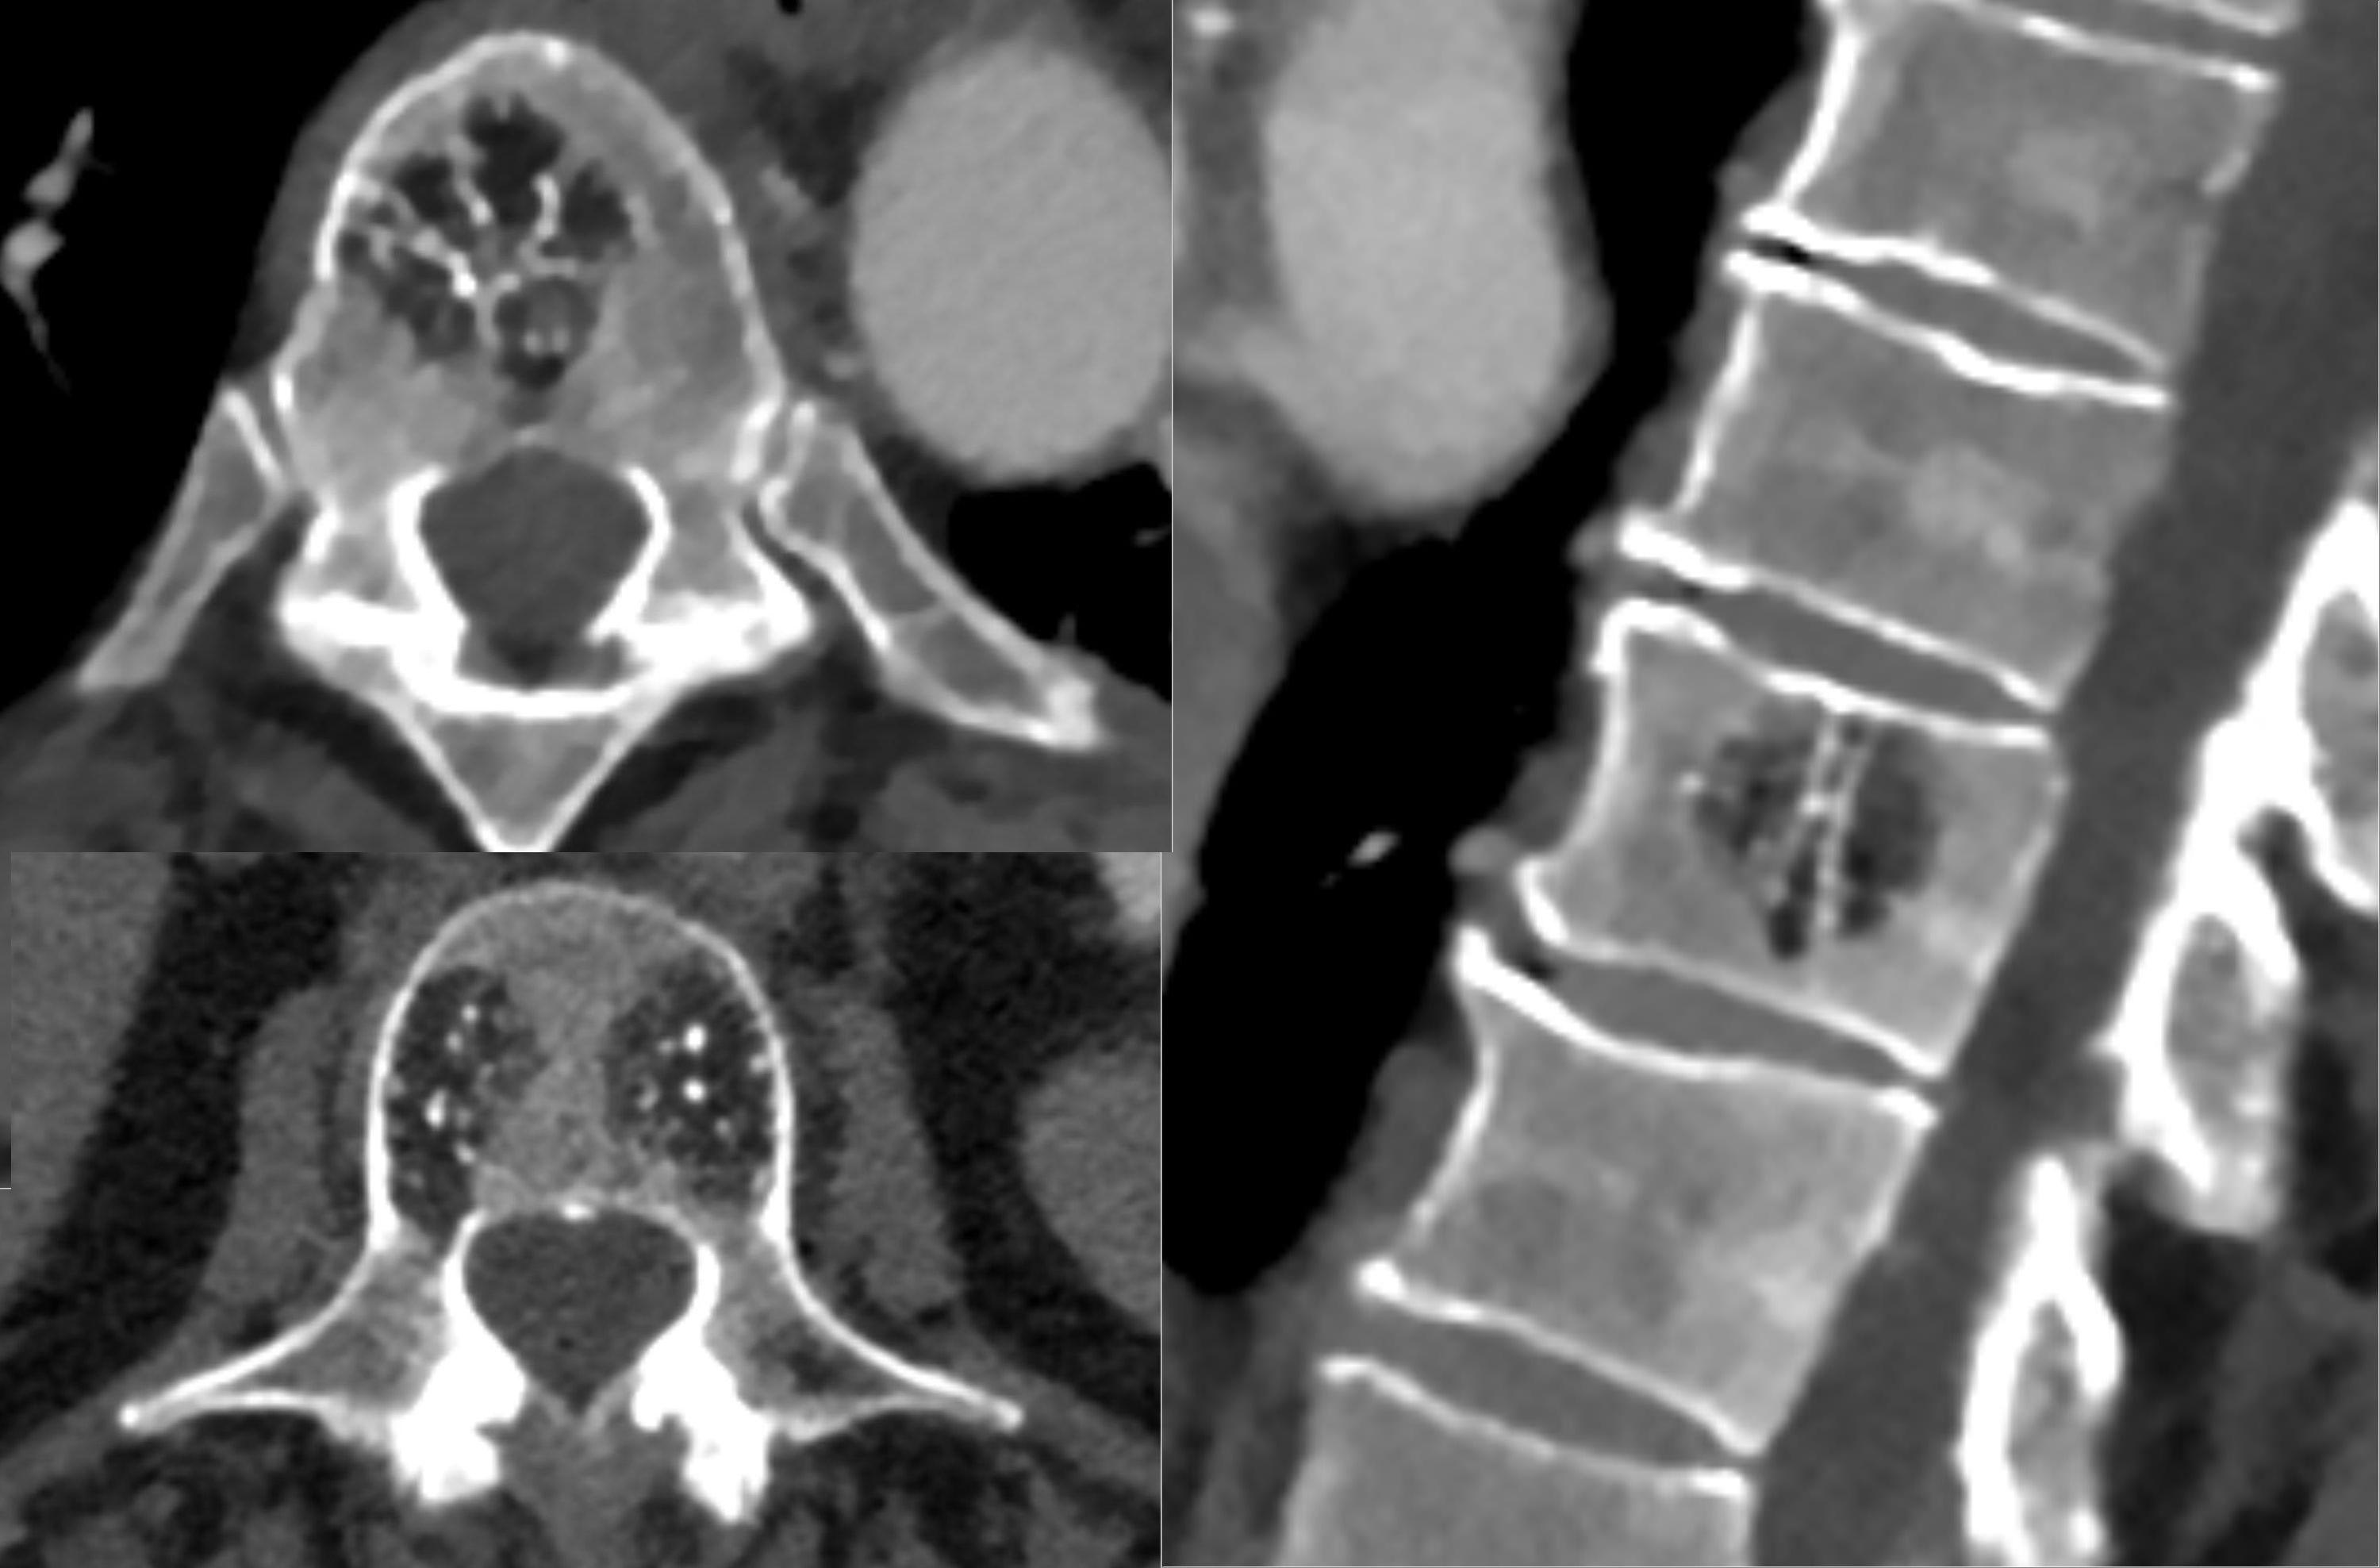

Annular Fissure Assessment and Treatment — Annular Disc Tear